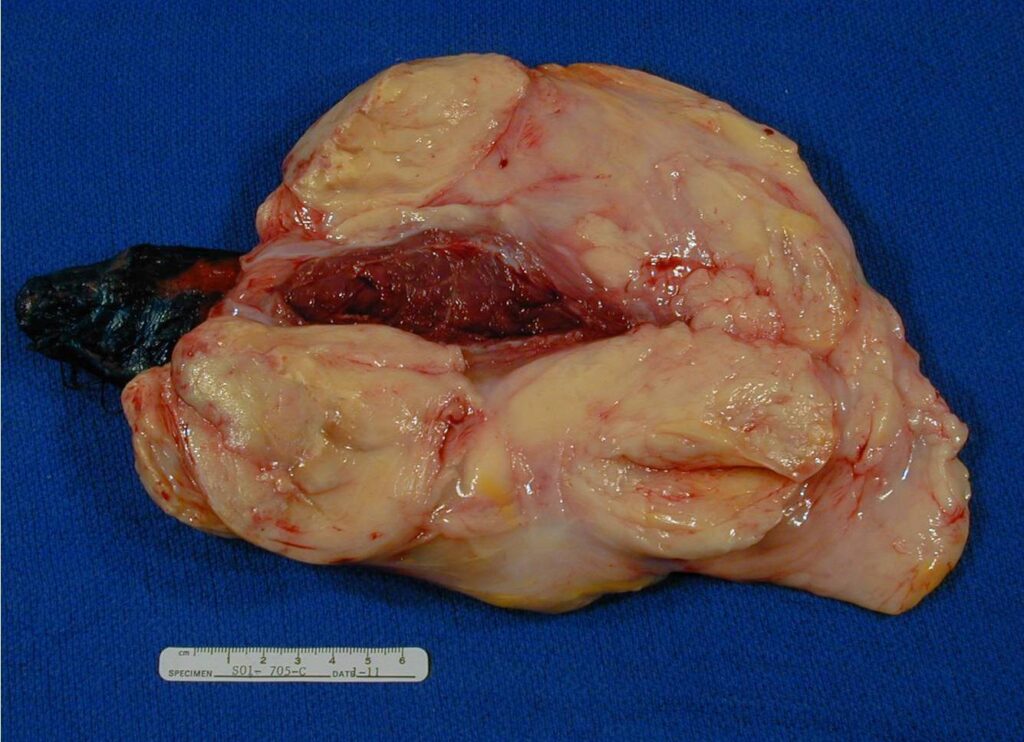

PATHOLOGY

Multinodular growth within and between skeletal muscle

• Soft and pale yellow on cut

Microscopic Pathology (Fig. 6, 7, 8)

Fig. 6-8 Microscopic Pathology. Low (Fig. 6), medium (Fig. 7) and high (Fig. 8) magnification H & E slides. Atypical stromal cells and lipoblasts in the context of mature fat. Often with a prominent fibrotic component and stranding. Higher magnification shows disorganized stromal cells and hyperchromasia of nuclei.

• Surgery is the mainstay of treatment. The most reliable means of obtaining local tumor control is by surgical excision with a wide excision if possible however most are marginally excised. (Fig. 9-13)

Fig. 9-13 Intraoperative. Wide Resection of an intermuscular Well Differentiated Liposarcoma.